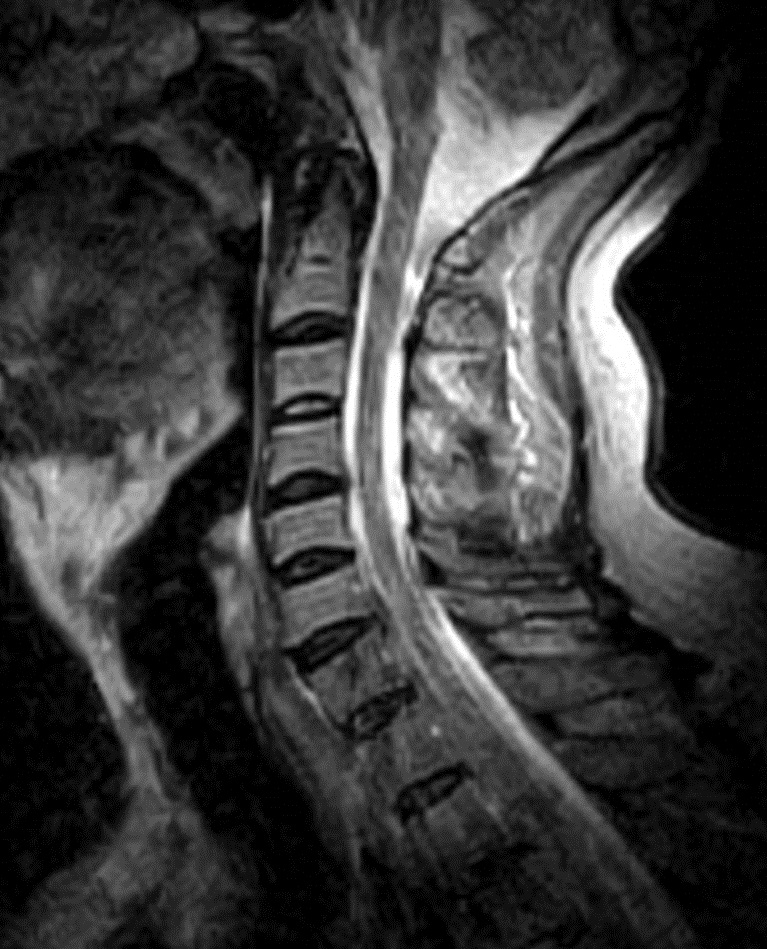

I have provided some select images from the MRI study that was obtained. Initially, the study was ordered non-contrast. Fig. 1 is a midline T-2 weighted image. It demonstrates a degree of posterior disc bulging at C6-C7. No focal posterior discal prominence was noted that would indicate a herniation. Fig. 2 is a gradient echo weighted image through the C6-C7 disc space. In this image, there is obvious expansion of the left intervertebral foramen with a degree of erosion of the facet at the posterior margin of the foramen. The signal intensity is bright on this image, compared to the normal intermediate signal intensity noted within the right foramen. You will note a degree of irregularity at the posterior margin of the disc in this cut, consistent with the disc bulging seen on the sagittal images. There is not sufficient encroachment of the central canal however to account for a neurologic deficit. A left parasagittal STIR image (Fig.3) reveals an obvious focus of abnormal signal within the left C6-C7 IVF that corresponds to the finding that was noted on the axial image. The signal intensity of this area was high on the STIR, gradient echo, and T-2 weighted images, and low on the T1 weighted images, consistent with fluid. At this point what diagnoses would you entertain, and would you order any follow-up imaging or testing?